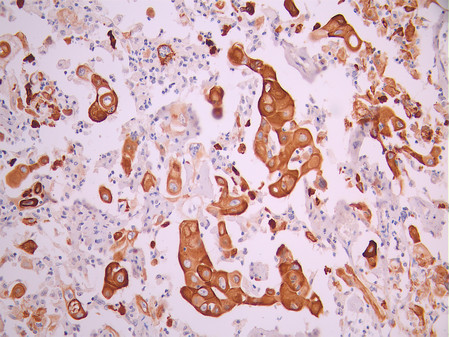

• IHC image of CSB-RA049199A0HU diluted at 1:100 and staining in paraffin-embedded human cervical cancer performed on a Leica BondTM system. After dewaxing and hydration, antigen retrieval was mediated by high pressure in a citrate buffer (pH 6.0). Section was blocked with 10% normal goat serum 30min at RT. Then primary antibody (1% BSA) was incubated at 4°C overnight. The primary is detected by a Goat anti-rabbit polymer IgG labeled by HRP and visualized using 0.05% DAB.